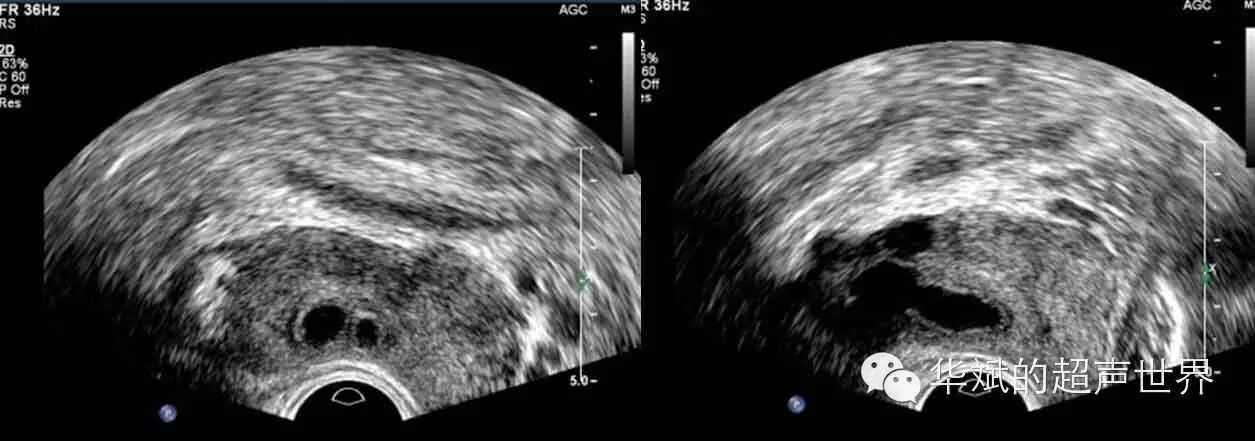

图3 双侧射精管囊肿,左图:经直肠横断。右图:经直肠旁正中矢状断(偏右侧)